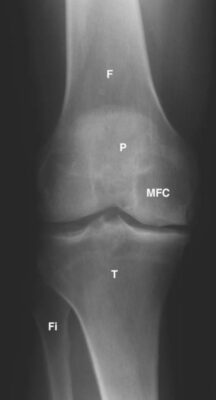

LIÊN HỆ X QUANG KHỚP GỐI

Ghi chú viết tắt:

- F = Femur; Xương đùi

T = Tibia; Xương chày - P = Patella; Xương bánh chè

- Fi = Fibula; Xương mác

- MFC = Medial femoral condyle ; Lồi cầu trong xương đùi

- TT = Tibial tubercle; lồi củ xương chày

- FT = Femoral trochlear groove; rãnh ròng rọc xương đùi

- A = Anterior cruciate ligament; ACL, dây chằng chéo trước

- B = Posterior cruciate ligament; PCL, dây chằng chéo sau